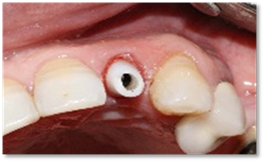

Endo-buccal examination (Figure 1) revealed the presence of the 22 roots.

Figure 1: Occlusal view of the maxilla showing the fractured crown of 22.

The patient returned for her third appointment, corresponding to the surgical phase of treatment. After disinfecting the incisive-canine area, local anesthesia was administered. The maxillary left lateral incisor (tooth 22) was then atraumatically extracted to preserve the vestibular bone. (Figure 4) Following extraction, the surgical guide was positioned and stabilized, and the drilling sequence was initiated for the placement of a 3.6 mm × 12 mm Biotech implant (Figure 5).

Figure 4: Atraumatic extraction of the 22.